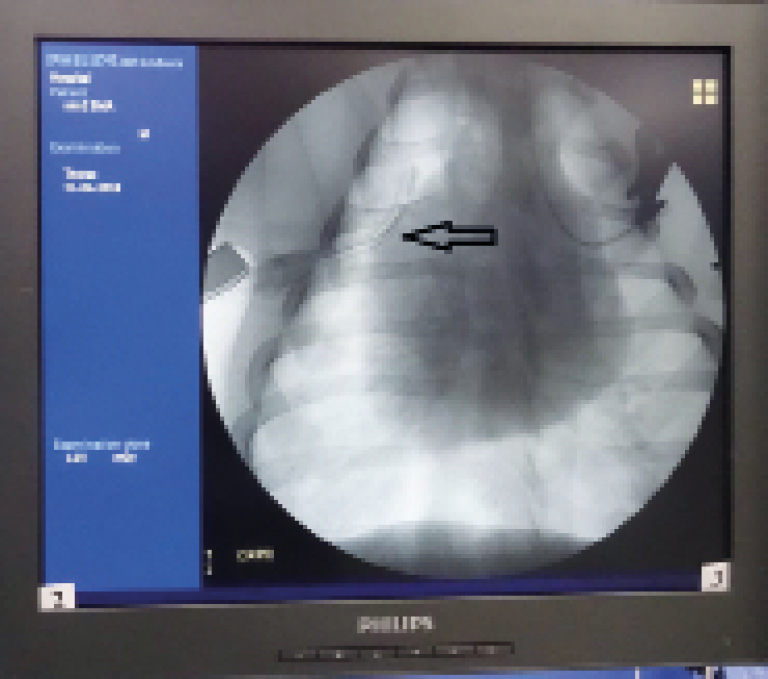

Оценивались объем забранной крови и данные рентгенограммы груди для определения ликвидации гемоторакса (рис. 7, 8).

Рис. 8. Рентгенограмма груди. Гемоторакс устранен, катетер визуализируется в VIII межреберье